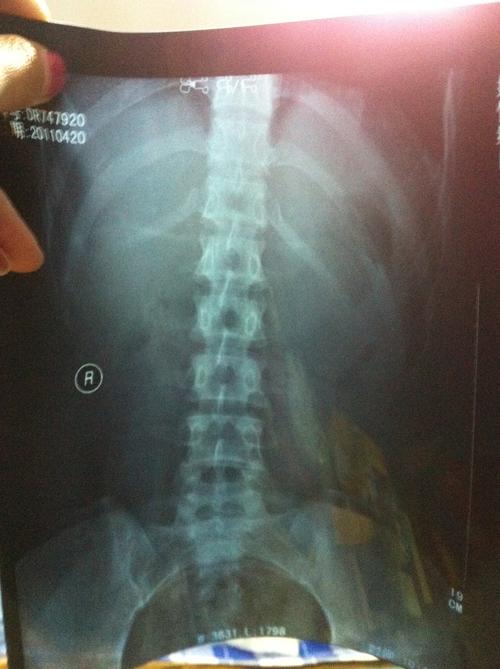

腰部骨头,骶骨痛

拍了片子,骨头无伤,脊椎正常,医生只让静养.可是疼.

腰部骨头图

腰部骨骼结构图

腰部骨头名称分布图